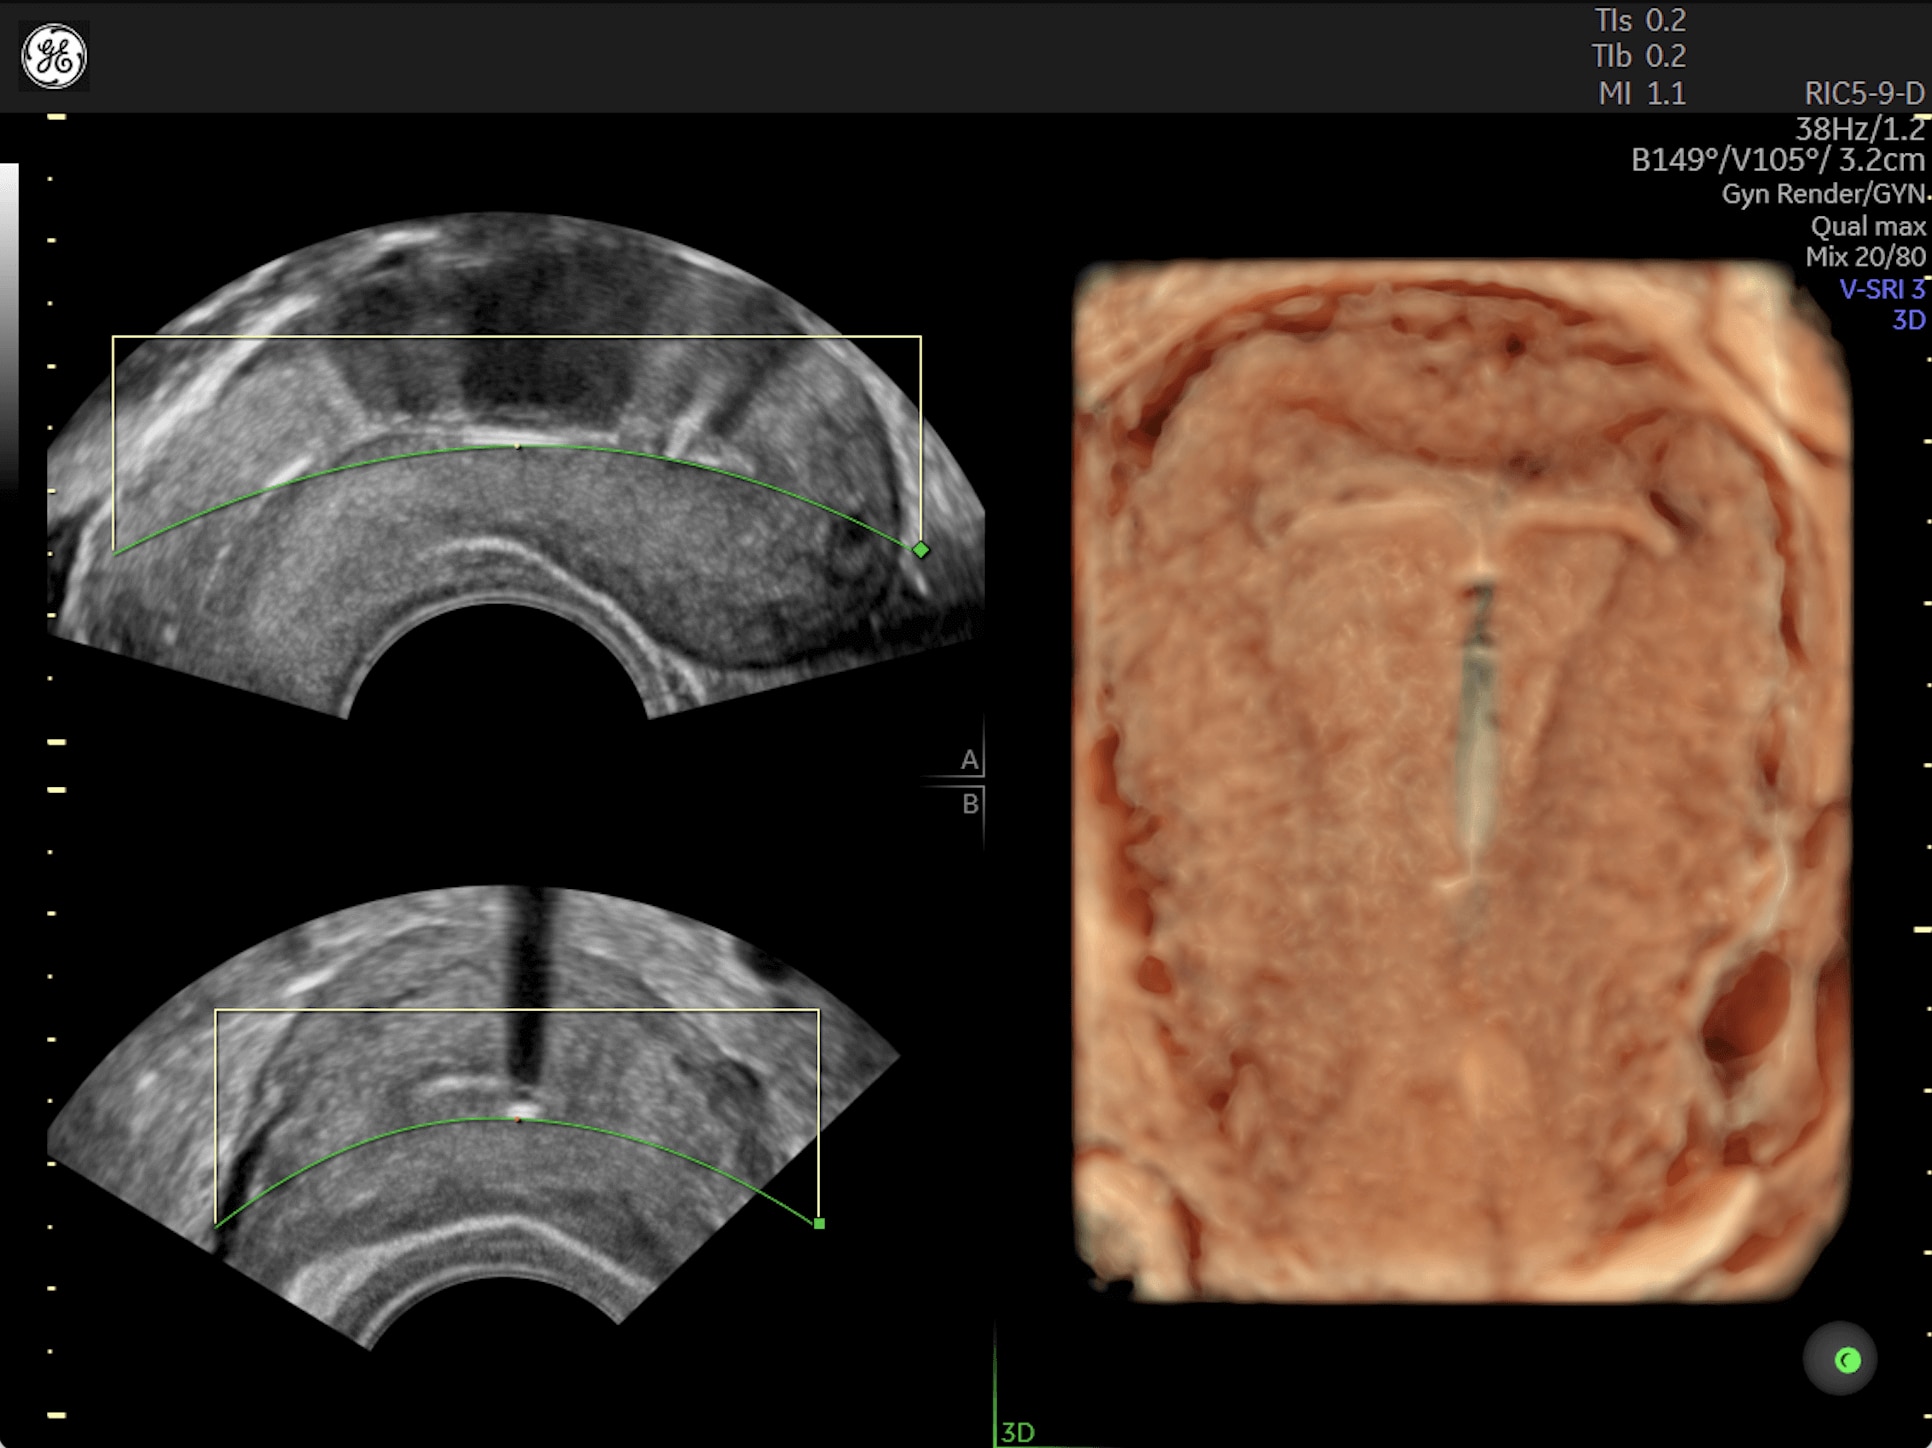

Amplify imaging performance and simplify scanning with our most advanced architecture

Extraordinary clarity and definition so you can focus on early detection and intervention.

Faster.Sharper. Clearer.

Faster.Sharper. Clearer.